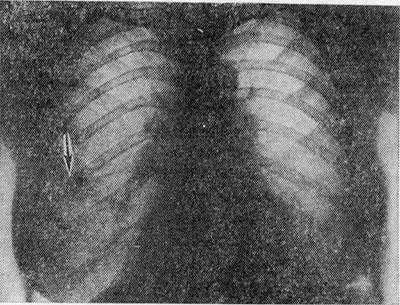

Рис. 1. Рентгенограмма грудной клетки больного с синдромом Леффлера: одиночный инфильтрат в правом легком (указан стрелкой).

Наиболее типичным рентгенол, проявлением Л. с. является тень одиночного инфильтрата, расположенного в любом отделе легкого, небольшой или средней интенсивности и, как правило, ее размеры 3—4 см в диаметре. Форма тени обычно неправильная, очертания нечеткие (рис. 1). Окружающий легочный рисунок усилен в связи с местной гиперемией. В большинстве случаев тень соответствующего корня легкого слегка расширена, структурна. При многопроекционном исследовании удается установить, что инфильтрат располагается чаще в плащевидном слое легкого. В связи с этим нередко можно выявить утолщение плевры, расположенной в непосредственной близости к инфильтрату. Характерным для динамики инфильтрата при Л. с. является его исчезновение через 1 — 3 дня после выявления; на месте бывшего инфильтрата в течение нескольких дней остается постепенно уменьшающееся усиление легочного рисунка. Такая быстрая динамика дала основание назвать эти инфильтраты летучими. Реже при Л. с. встречаются инфильтраты, принимающие форму анатомических структур — сегментов, долей, и множественные инфильтраты, к-рые иногда могут быть двусторонними (рис. 2). Быстрое исчезновение является типичным для всех видов инфильтратов при Л. с. В относительно редких случаях инфильтраты могут рецидивировать. В отдельных случаях при наличии крупных инфильтратов можно обнаружить небольшой транссудат в плевральной полости, к-рый рассасывается в течение нескольких дней.